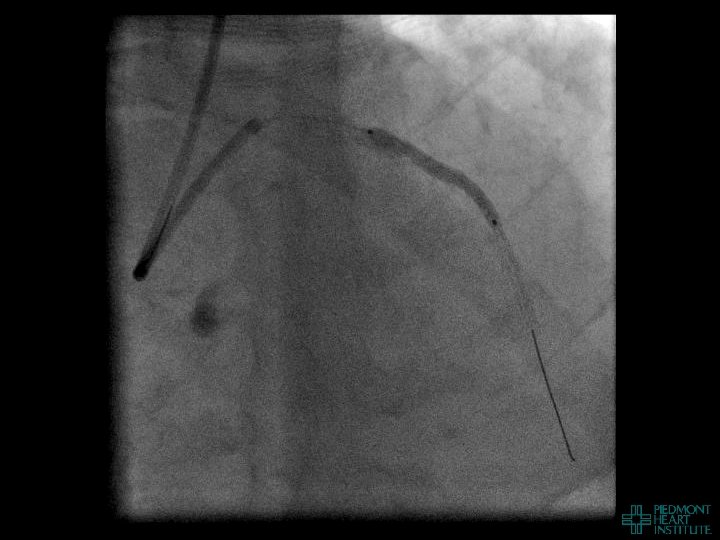

Coronary Perforation Methods of Patient Management • Dual Catheter (‘Ping Pong’) Technique • Prolonged

Coronary Perforation Methods of Patient Management • Dual Catheter (‘Ping Pong’) Technique • Prolonged balloon inflation and covered stents • Reversal of anticoagulation — Know contradictions to protamine sulfate for UFH; Avoid bivalirudin, LMWH — Reserve GP 2 b 3 a inhibition until successful crossing and wire change-out Embolization • — Coil, gelfoam, methacrylate, autologous blood/fat • Microcatheter Occlusion • Confirmation of successful management — Contralateral injection — Right heart catheterization — Echocardiogram — Contrast echocardiography